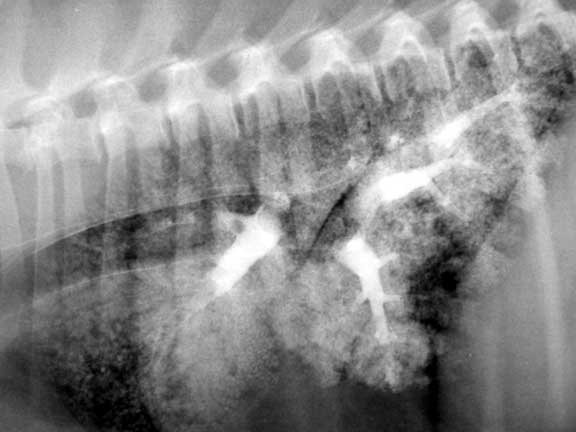

Side view of the abdomen showing severe fecal impaction in the colon called obstipation.

Fluid in the abdomen called ascites. Notice that you cannot see the individual internal organs.

Fluid in the chest called pleural effusion